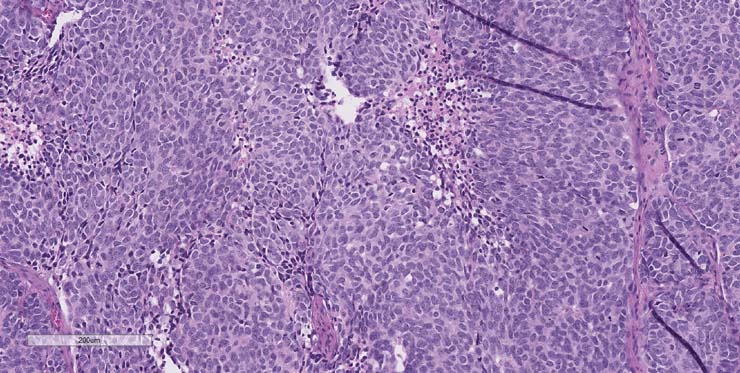

P1 pathology consistent with a metastatic and highly treated Ewings Sarcoma with aberrant cytokeratin expression. P2 Pathology consistent with Ewings Sarcoma.

P1 tumor F001 ID007 for PDX model J000109079 stained for H&E.